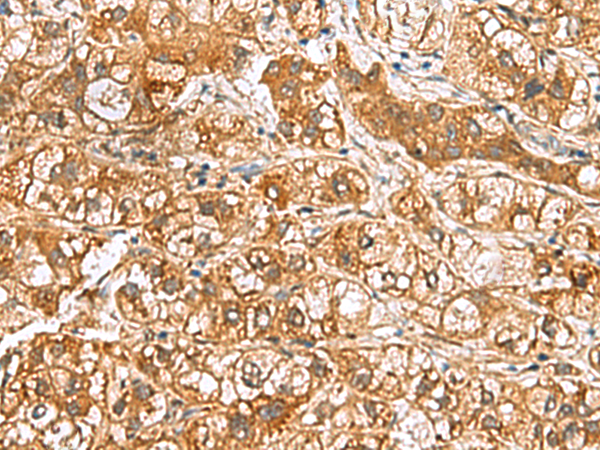

ELISA, WB, IHC

IHC positive control:

Human lung cancer and Human liver cancer

IHC Recommend dilution:

50-200